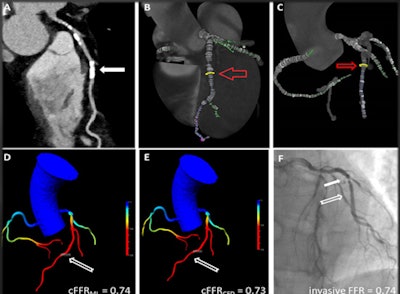

In a 53-year-old man with chest pain, both CCTA and invasive coronary angiography showed 50% stenosis of the middle left anterior descending (LAD) artery, while cFFRML and cFFRCFD showed a greater degree of stenosis, at 74% and 73%, respectively. Image courtesy of Dr. Moritz Albrecht.Both algorithms performed better than CCTA and quantitative coronary angiography (p < 0.04); however, there were no significant differences between cFFRML and cFFRCFD receiver operating characteristic (ROC) curves (p < 0.95).